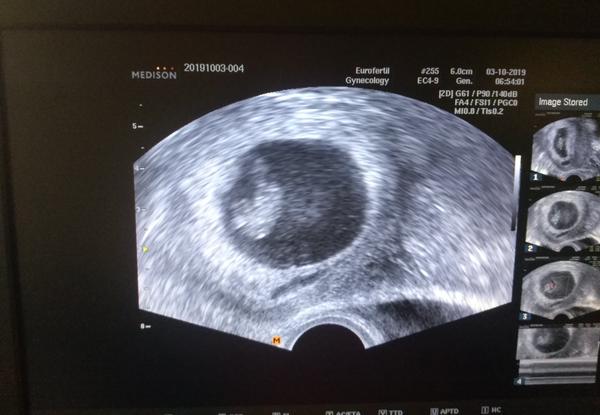

Ahoj,tak dnes kontrolni ultrazvuk...Mudr. Mardesicova byla nadsena,ja zase tolik ne...vypada to tak na 8-10 folikulu,odber v patek.Pane boze,prosim,at to vyjde🙂Uz bychom si to zaslouzili...